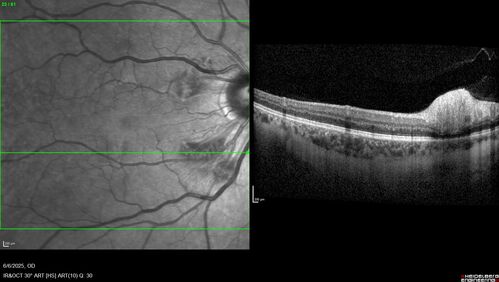

Cotton Wool Spots following cardio-pulmonary bypass

The patient had emergency thoracotomy about 3 weeks ago he had an aortic dissection with a root aneurysm. It had dissected down to the iliacs. The patient had a thoracotomy and aortic valve replacement and large aortic graft.